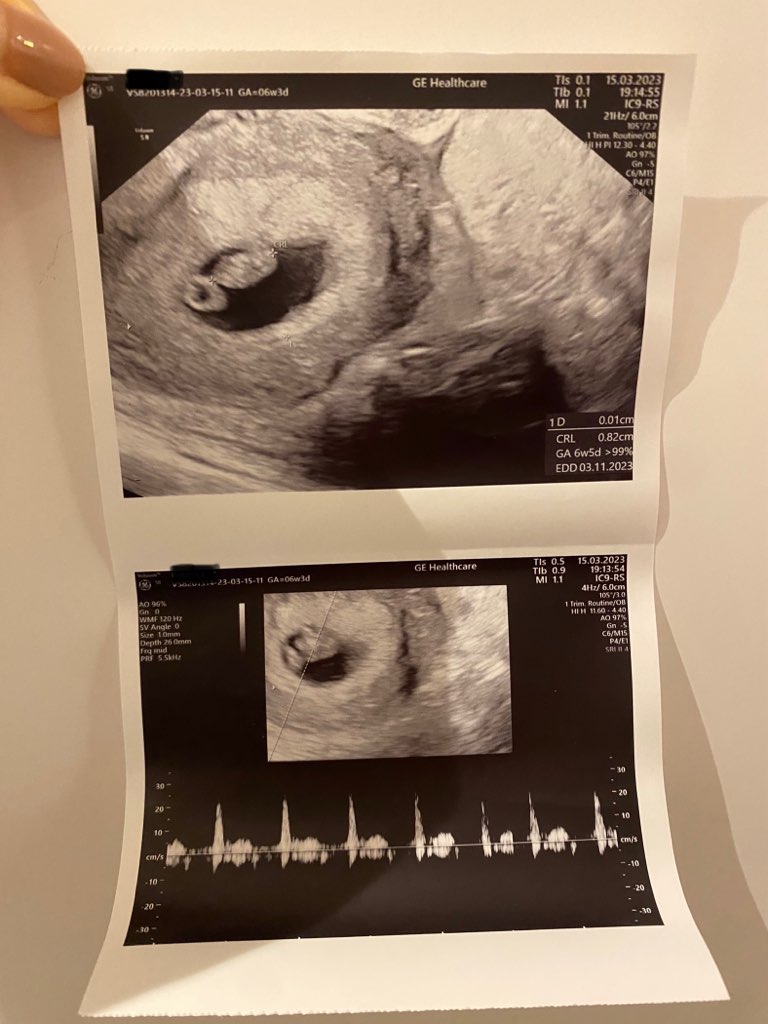

Cześć Laseczki, jednak byłam dzisiaj u ginekologa i wszystko w najlepszym porządku ❤️ biło serducho 119 uderzeń na minutę, jeśli chodzi o wielkość zarodka to tez odpowiednio, 0,82cm ❤️

Wg badania 6+5, a wg OM 6+4 wiec tez żadna różnica ❤️ jestem taka szczęśliwa!

Buziaki dla Was ! Zostawiam foteczke mojej Fasolci